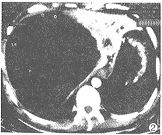

CT示:肝内见一巨大类圆形肿块,直径大小约16.5cm,边界尚清晰。其内以囊性为主,囊壁有乳头状实性突起及少量实性分隔(图1)。增强扫描见纤维间隔有强化(图2)。

图1 肝内一巨大类圆形肿块,边界尚清晰,其内以囊性为主,囊壁有乳头状突起及少量实性分隔